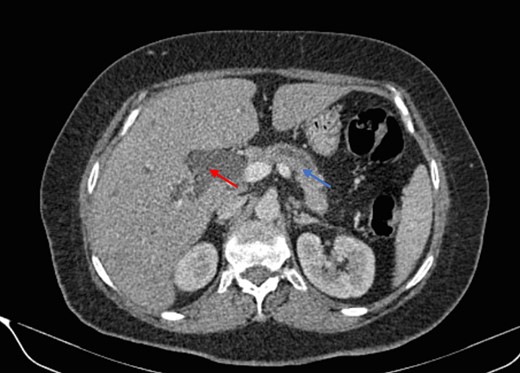

Mr. B. is a 59-year-old patient with no notable pathological history, presenting with melenas associated with marked weight loss. A fibroscopy revealed a thickened and ulcerated gastric mucosa. Abdominal and pelvic CT scans revealed a tissue process in the body and tail of the pancreas invading the splenic hilum, adjacent vessels ans gastric wall, measuring 11 cm long (Fig. 5). A caudal spleno-pancreatectomy enlarged to the colon, omentum and stomach was performed. Macroscopically, the tumor had a grayish–white appearance, poorly limited and indurated on palpation. Histologically, it was a well-differentiated, keratinizing squamous cell carcinoma of the tail of the pancreas (Figs 6 and 7), infiltrating the splenic hilum, gastric wall and colon.

Low enhancing mass at pancreatic body and tail with internal necrotic changes. The mass encases the AMS and its branches and encases splenic vessels. Loss of the fat plane between the mass and adjacent spleen.